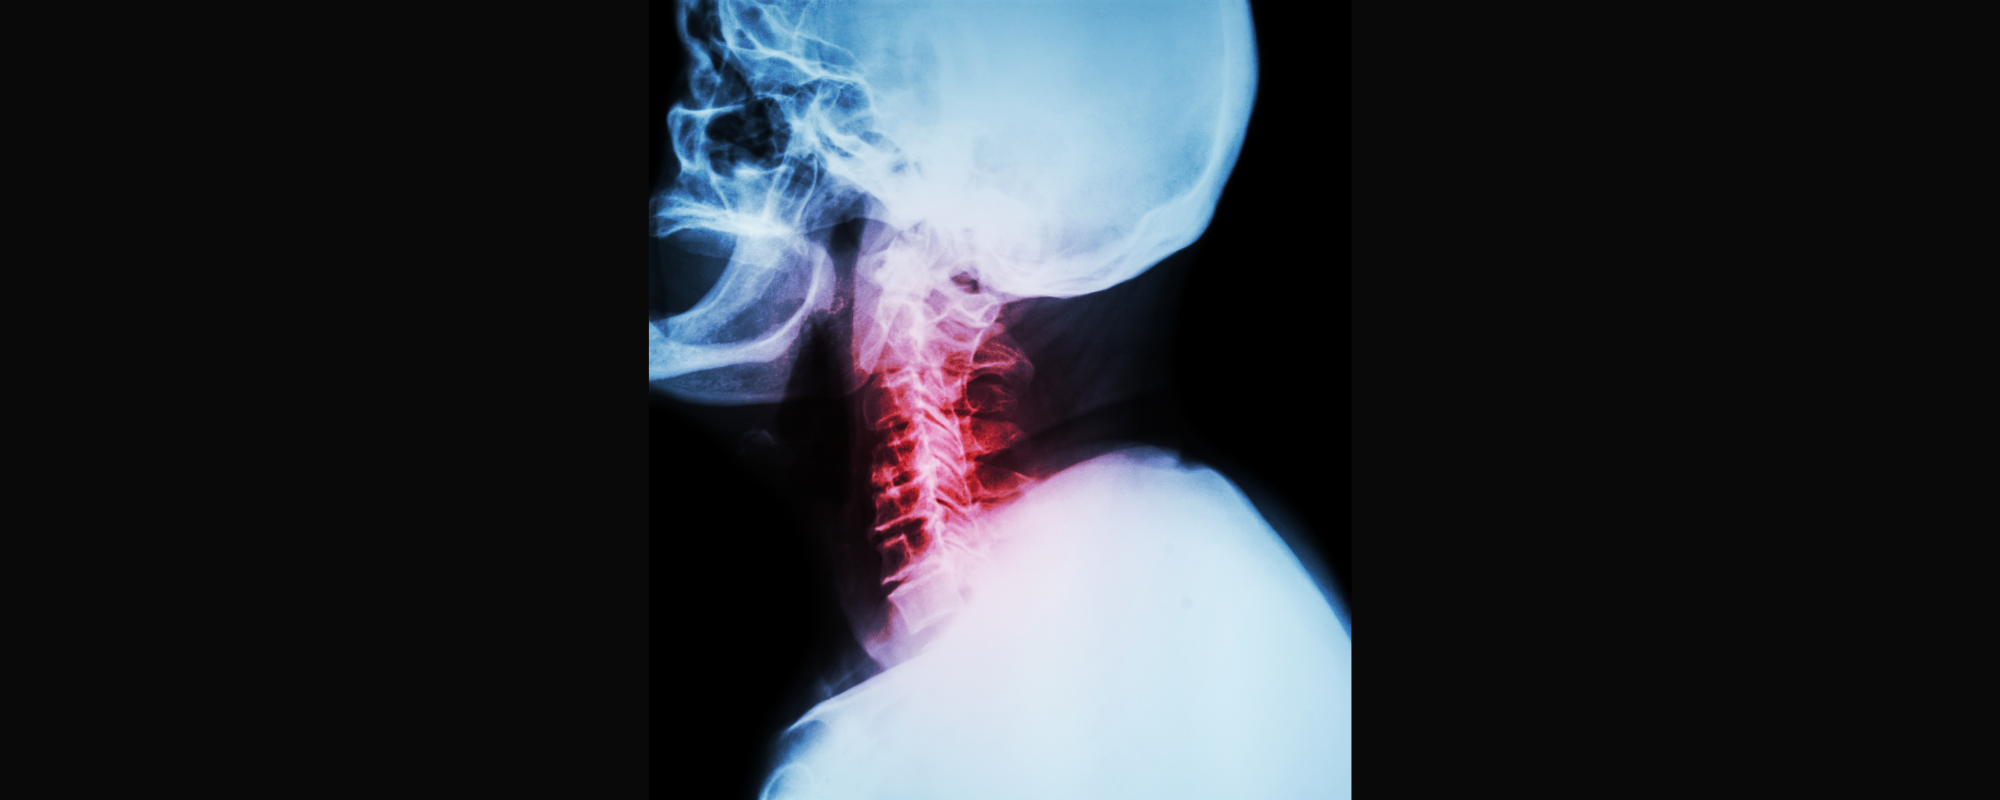

Boyun Fıtığı Nedir?